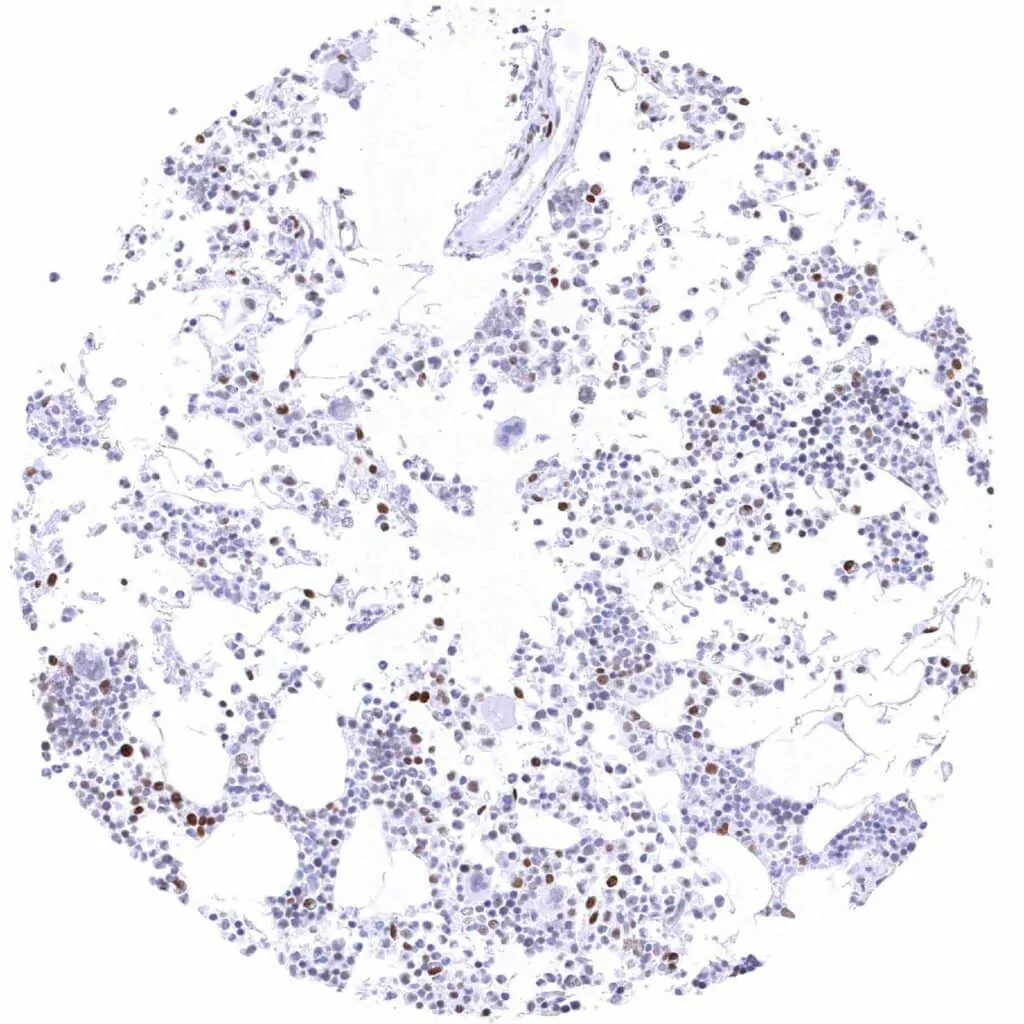

Bone marrow – Weak to strong TLE1 positivity of a significant fraction of cells-1